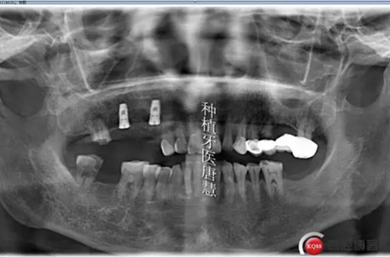

術(shù)后片

術(shù)后第二天回訪無明顯腫痛。